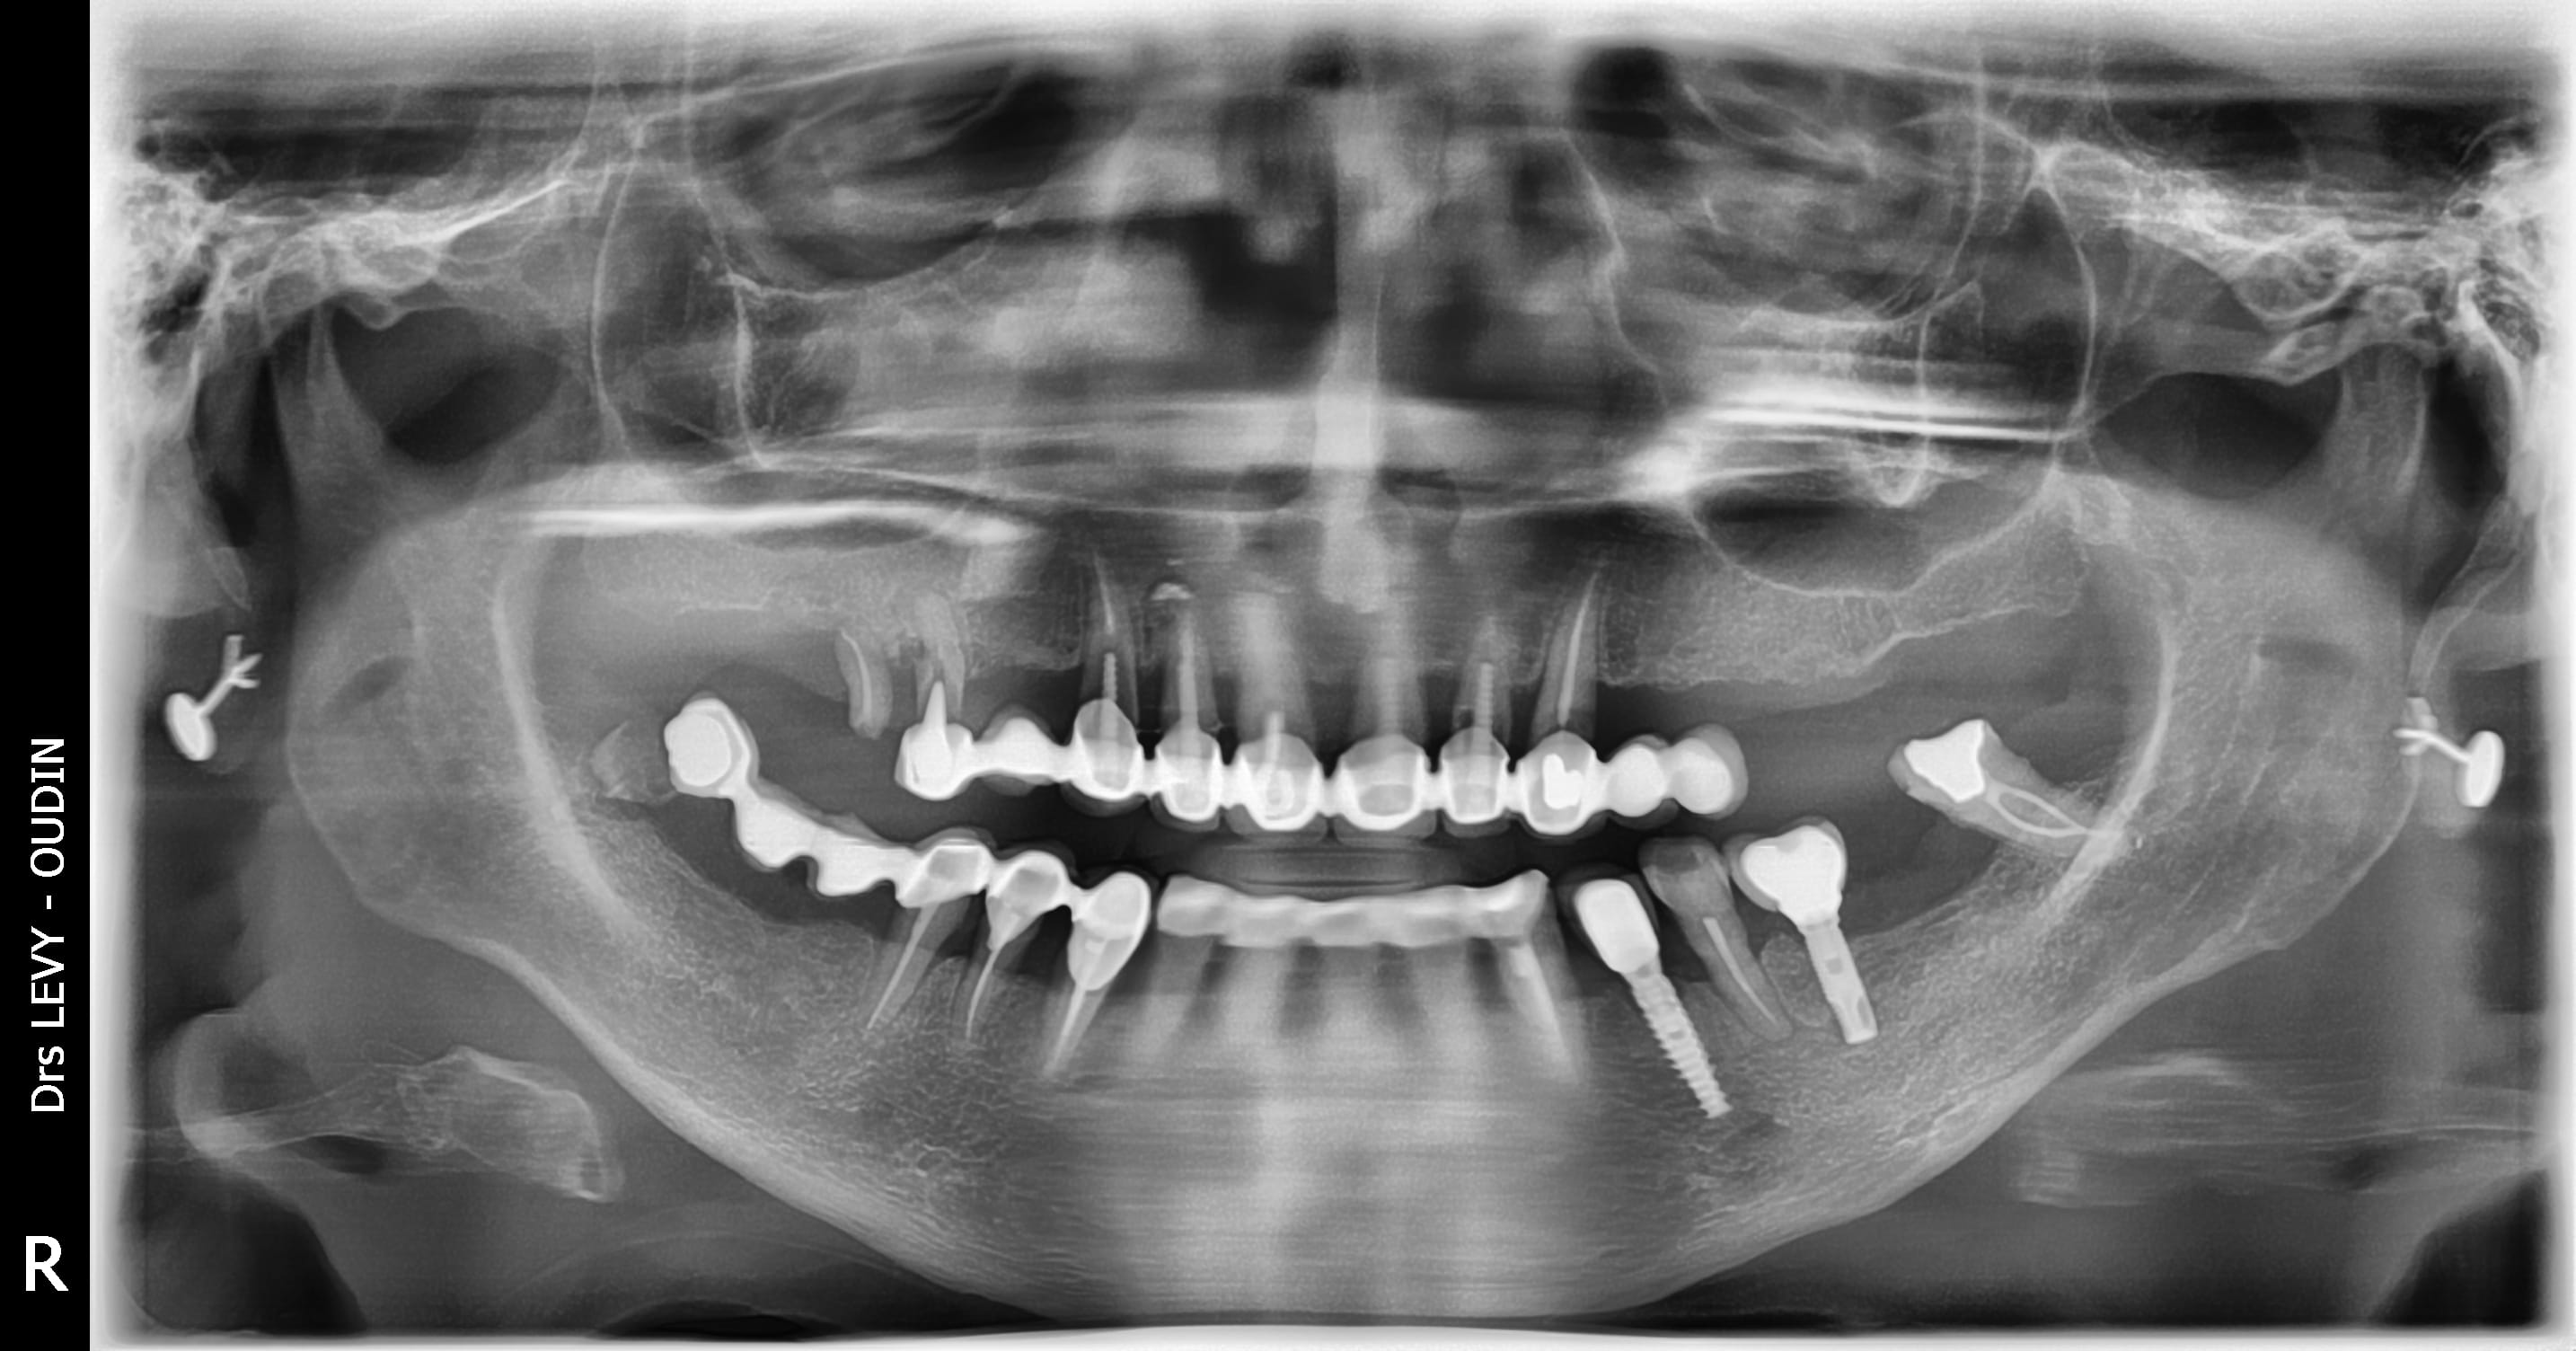

Avant de pouvoir payer ma facture d'éléctricité, si une âme charitable pouvait m'identifier l'implant 34 (36 est un branemark je pense), celà m'aiderait grandement.